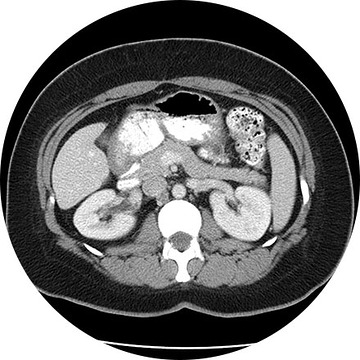

Enterography

This is an accurate and noninvasive imaging procedure used to assess and evaluate certain gastrointestinal problems, such as inflammatory bowel disease (including Crohn’s Disease), infectious enteritis, lymphoma or tuberculosis. It also can be used in patients with gastrointestinal bleeding to determine if a small bowel polyp is causing the bleeding. Enterography may be performed using MRI or CT.